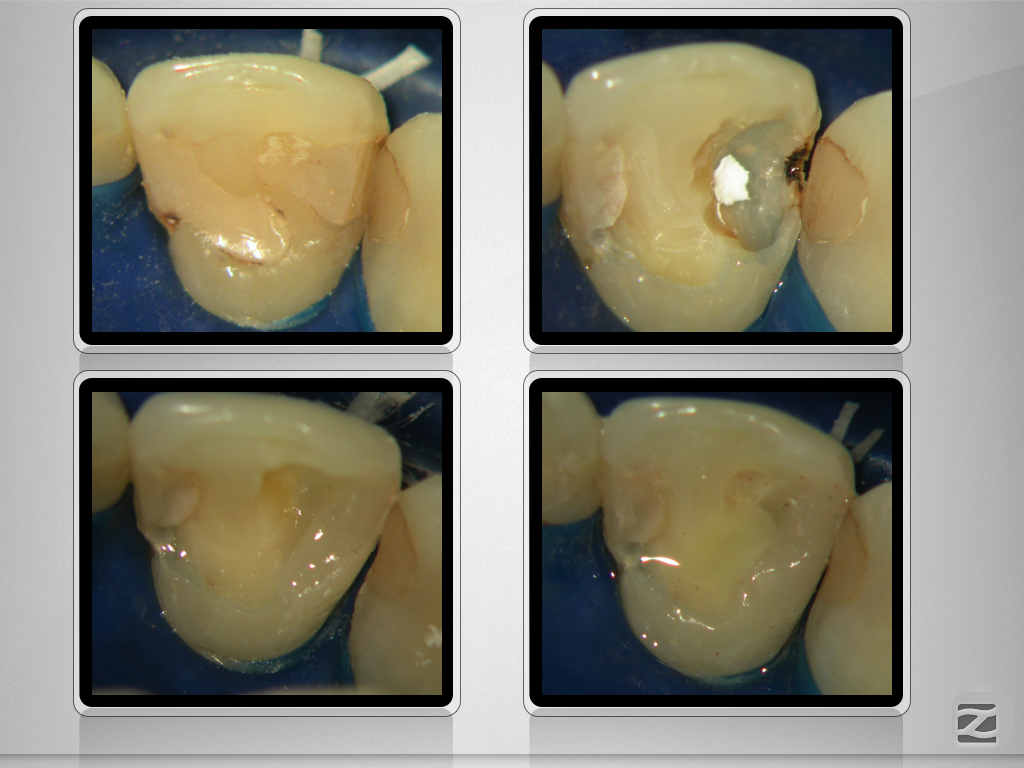

Perforierende interne Resorption